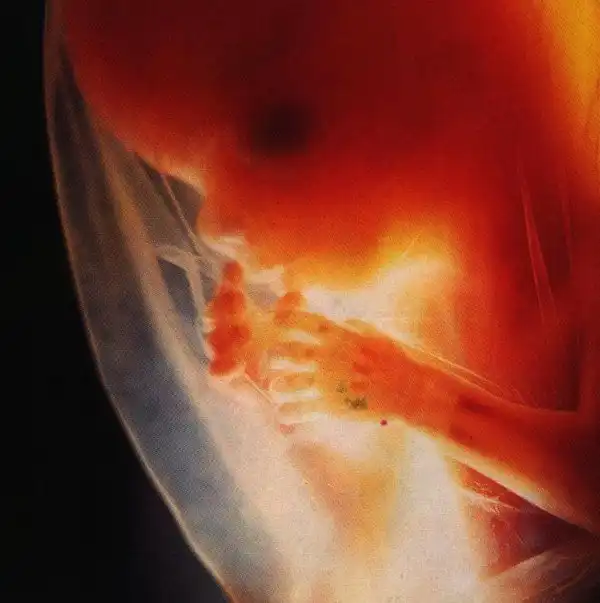

У мамы в животике)